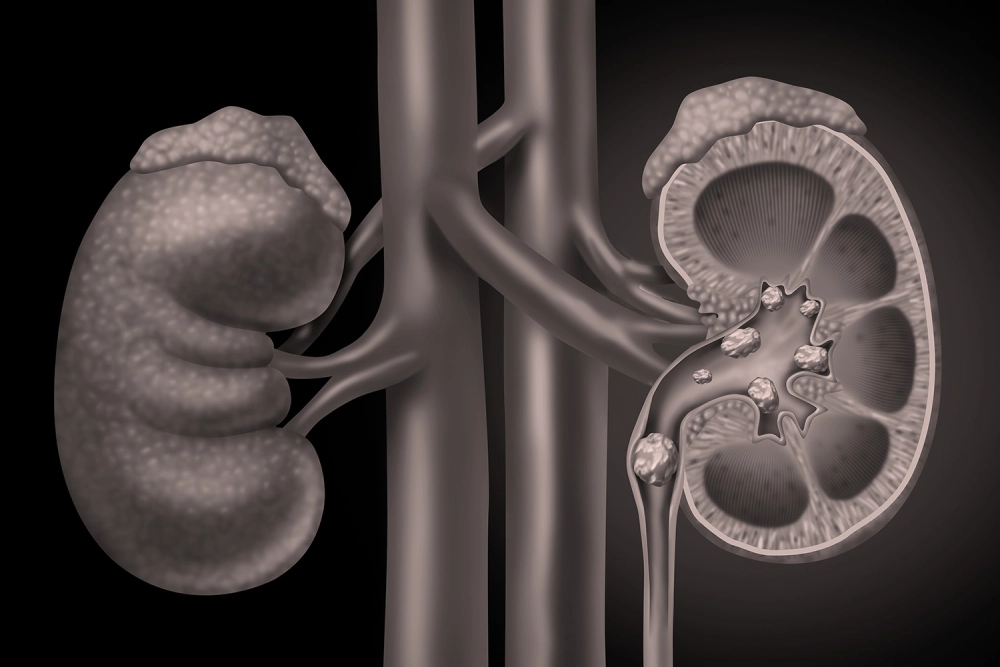

Kidney Stones & Stone Disease

Kidney and ureteric stones can be incredibly painful and disruptive of daily life appropriately managed, however, treatment can be targeted, safe, and less invasive than most imagine.

Patients looking for a Kidney Stone Specialist in Mumbai trust Dr. Jeena KR’s evidence-based care. She applies modern medicine and technology to treat and prevent stone disease. She provides a comprehensive patient evaluation including imaging (CT, Ultrasound) and metabolic work up, which is vital in identifying stone size, location, and potential medical causes.

She employs techniques such as Lithotripsy (either laser or pneumatic assisted), Flexible and Semi-rigid Endoscopy (URS, fURS / RIRS) and Percutaneous Nephrolithotomy (PCNL). Each of these techniques is a minimally invasive procedure where stones are removed or broken, using small instruments. In most cases, these techniques have less recovery time and fewer complications than alternatives.